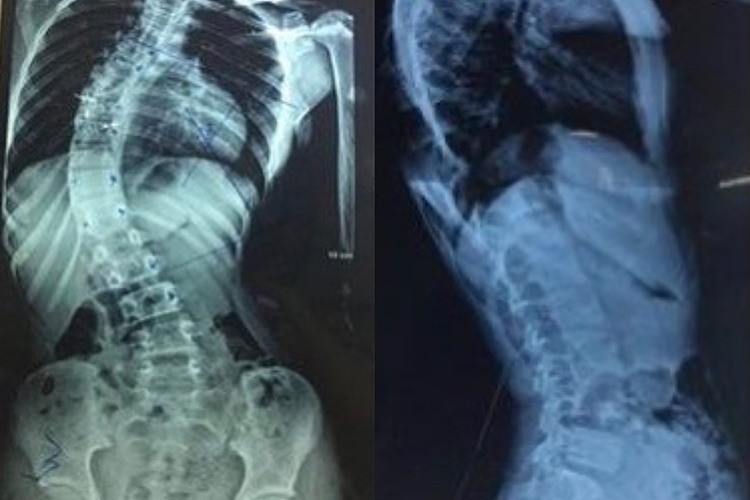

Ảnh chụp X-quang cột sống vẹo 45 độ trước phẫu thuật. Ảnh: Bệnh viện cung cấp

Tiến sĩ, bác sĩ Nguyễn Văn Sơn, Phó giám đốc Bệnh viện, cho biết người bệnh bị vẹo cột sống nặng với đường cong lớn hơn 45 độ, thường cần phẫu thuật, phổ biến nhất là hợp nhất cột sống. Bác sĩ phẫu thuật sử dụng thanh kim loại, móc, ốc vít và dây để điều chỉnh đường cong cột sống, bảo vệ cột sống ở vị trí thẳng trong khi chờ chúng lành lại và trở nên rắn chắc.

Cũng theo bác sĩ, đây là trường hợp góc cột sống lệch trên 45 độ, tức độ cong khá nhiều, cần phải phẫu thuật mới trả lại được nếp bình thường.